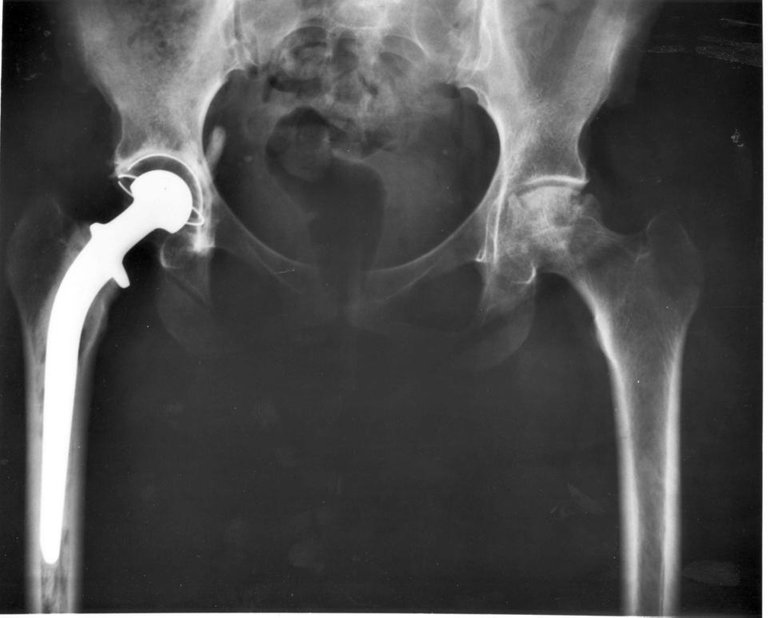

Hip_replacement_Image_3684-PH.jpeg

Image de radiologie montrant une prothèse totale de hanche

Crédit : By X-ray Image ID: 3684. Photographer: Unknown. [Public domain], via Wikimedia Commons

Le traitement chirurgical doit être proposé chez les sujets jeunes et/ou lorsque l'arthrose est très invalidante. Ce sont les interventions les plus réalisées en France avec respectivement 150 000 et 100 000 poses de prothèse par an pour la hanche et pour le genou.